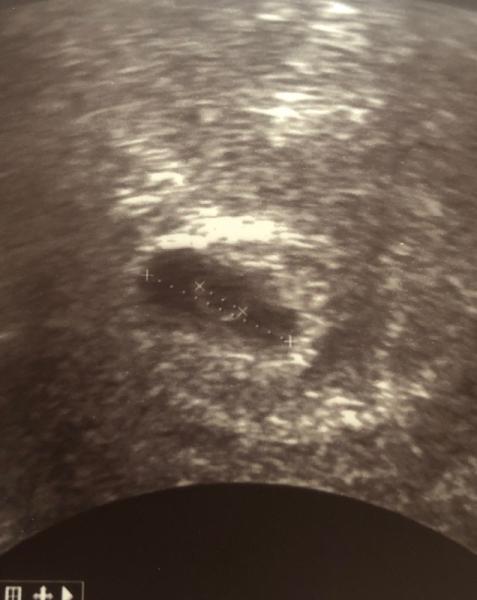

Hallöchen, Ich bin eine stille Leserin :) aber ich muss mich heute mal entleeren Ich habe am 01.05. pos getestet, wollte dann aber noch mit dem Termin warten aber mein Fa wollte mich eine Woche später schon sehen... Termin war am 06.05. Meine Schleimhaut war wie erwartet aufgebaut aber eine Fruchthöhle noch nicht zu sehen ( dachte ich mir ) laut Rechnung 4+4 Heute wieder hin bei 6+4 rechnerisch aber man hat auch nur ne Fruchthöhle und Dottersack gesehen kein Embryo:( Er stufte mich darauf hin auf 6+0 runter ( laut Messung der Fh) Jetzt bin ich verunsichert Kann mir einer sagen was ich davon halten soll

Bild zu Heute 2 Fa Termin ... - Forum für Januar - Mamis